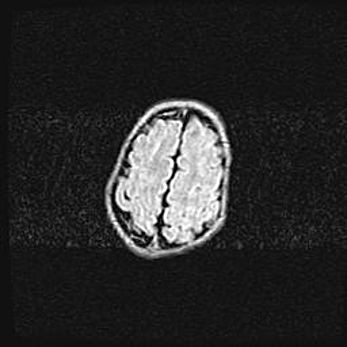

Сообщающаяся гидроцефалия. Кистозная энцефаломаляция головного мозга.

Возраст: 3 месяца 4 дня

Вес: 3100 г

Пол: женский

Окружность головы: 34 см

Срок гестации: 31 неделя

Кистозная энцефаломаляция головного мозга - одна из форм поражения головного мозга в детском возрасте. Характеризуется возникновением множественных и распространённых кист в коре, белом веществе и подкорковых образованиях головного мозга у плодов, новорождённых и детей раннего возраста. Развитие кистозной энцефаломаляции связано с внутриутробной асфиксией и гипотонией, родовой травмой, тромбозом синусов, пороками развития сосудов, инфекциями, сепсисом и другими причинами. Наиболее значимые инфекционные агенты: вирусы простого герпеса, цитомегалии, краснухи, токсоплазмы, энтеробактерии, золотистый стафилококк и другие.